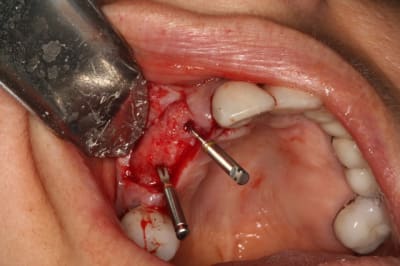

Ce sera un bridge sur 2 implants

Il y avait pas de gencive attachée au buccal de la zone.

Greffon AlloDerm, 2 pins au centre (car je ne voulait pas taper dans les implants, extension-tunnel en mésial et distal, sutures.

Parce que ça bouge moins, et que la patiente porte un stellitte temporaire par dessus...

puis j'avais 2 pins en trop